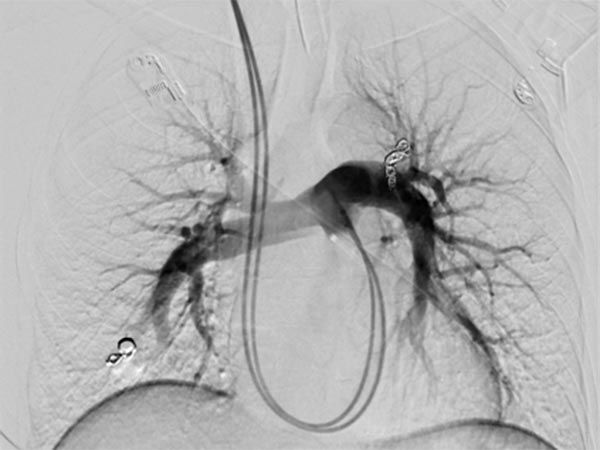

A guiding sheath was inserted into the right pulmonary artery from the neck (transjugular) via the heart, and a coaxial catheter was inserted through this by the Seldinger technique. After injection of contrast medium, pulmonary AVMs are also seen in the right lower lobe of the pulmonary circulation.

After cannulization of the larger pulmonary AVM, dilatation of the direct arteriovenous communication in the form of an aneurysm is seen. This is typical of Osler’s disease. The venous outflow is dilated, thus the risk of thromboembolism is particularly high.

The feeding arteries are occluded with several coils. Parts of the coils are placed in the arterial feeding branch for secure anchoring (anchor technique). The pulmonary AVM is occluded. In the former aneurysm there is still some contrast medium stasis from a previous injection.

Completion DSA via the pulmonary trunk shows no more flow into the pulmonary AVMs.

Completion DSA via the pulmonary trunk in the parenchymal phase confirms complete occlusion of the pulmonary AVMs.